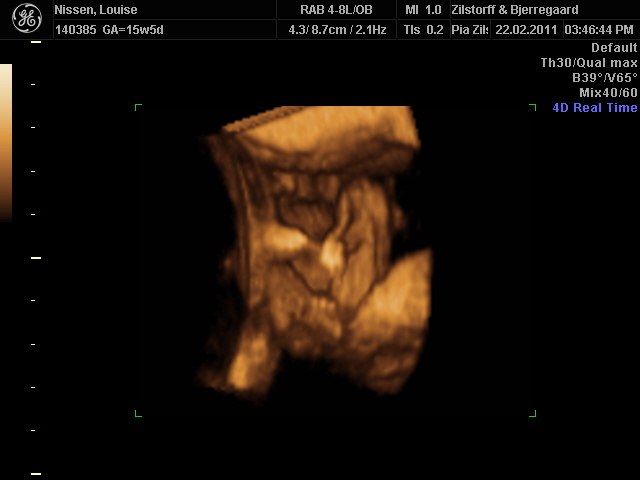

Måske er dette billede bedre

Ved du hva køn det er ? - jeg kan slet ikk se hva der er hoved eller hale hihi

Jeg aner tap ? Hvad er hoved og hale på billedet ??

Jeg kunne ikke finde ud af billedet før, men på dette billede ligner det at der er en tap der imellem benene Er det mon det rigtige svar?

Jeg tror det er en lille dreng

Men vil også oplyse at du ikke er heeelt hemmelig, der står jo navn på billedet, Louise